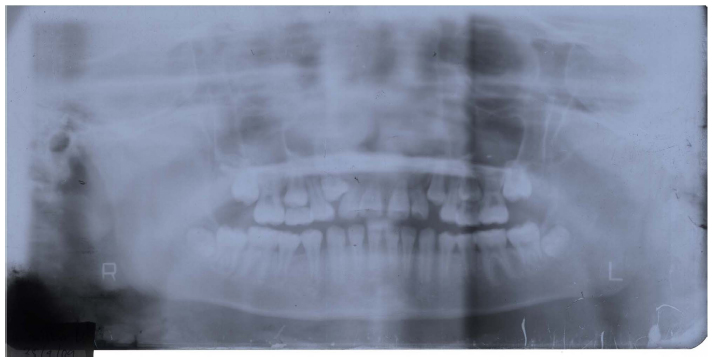

Facial examination showed a straight, slightly concave profile of the patient (Fig. 3). The patient had a Class I skeletal relationship (Fig. 4). Intraoral examination revealed that the patient was in the late mixed dentition stage, with maxillary crowding and moderate spacing in the mandibular arch (Fig. 3). It was observed that patient had an edge-to-edge anterior bite, Class II molar relationship with a bilateral posterior crossbite, and nonerupted upper canines (Figs. 3 and 4). Furthermore, the patient had good oral hygiene and no dental cavities. The panoramic radiograph (Fig. 4) demonstrated late mixed dentition, including a lack of space for the eruption of both maxillary canines.